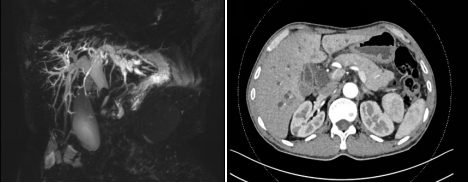

李大爷,今年65岁,因“上腹部不适半月,皮肤巩膜黄染10天”前往广元市第一人民医院就诊,入住肝胆甲乳外科。入院后,上腹部增强CT及MRCP提示:胆总管胰腺段管壁增厚、管腔狭窄,考虑胆管恶性肿瘤。

“针对患者病情,微创治疗是最好的选择,不仅可以放大手术视野,做到解剖清晰、精准手术,而且可以减少腹部切口的创伤,加速患者术后康复。”王少渊主任解释道。最终,经过科室多次讨论,本着“能微创治疗就不开刀”的理念,在征求家属的同意后,决定为其行腹腔镜胰十二指肠切除术(LPD)。该手术很复杂,需要切除多部位器官,再进行多部位切口的吻合,即便是开腹进行难度也极大,全腔镜下切除更是难上加难。